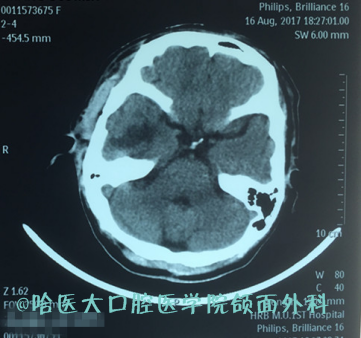

颅底介于头颅与颌面和五官之间,有重要的神经和血管穿行。颅底外科更是涉及神经外科、颌面外科、耳鼻咽喉科、整形外科、头颈外科及肿瘤外科的多学科、跨学科协作的典型代表学科。虽然在20世纪初,颅底外科便已有开展,但由于当时的各种条件及外科医生认知水平等因素的限制,术后往往出现脑脊液漏或颅内感染等严重并发症,这也使得颅底外科发展缓慢,更是成为颌面外科医生的“禁区”。90年代以来,随着显微外科的发展,颅底肿瘤已不再是不能手术切除或手术无法完整切除的禁忌。我科室的多位教授亦曾协助神经外科完成数例颅内肿瘤颅外段的手术,并取得良好的远期疗效。本病例中,我院吴衍昌教授团队首次在颌面部肿瘤侵袭颅底的情况下独立完成对颌面部及侧颅底病损的完整切除,是基于过硬的显微外科理论、知识及技术下外科综合能力的体现,标志着我院口腔颌面外科-侧颅底外科“0”的突破,填补省内空白的同时,更标志着我院颌面外科水平达到东三省内引领,国内领先水平。

2 占位突入颅中窝

6 术后一周后CT提示颅中窝病损切除彻底,未见明显渗出